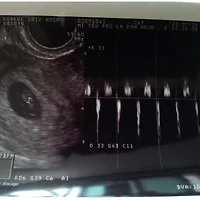

우제 아빠의 초음파 이야기 (0) | 2014.04.08 |